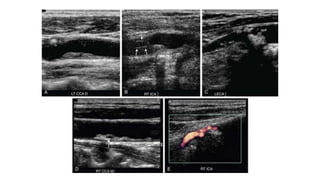

ULTRASOUND ASSESSMENT OF PLAQUE

• Ultrasound evaluation of plaque requires gray-scale and color Doppler imaging in

both longitudinal and transverse planes.

• Such images can be used to estimate percentage diameter reduction by plaque and

correlated with PSV measurements.

• In addition, the echotexture and surface contour of the plaque should be

assessed.

• Plaque should be characterized as hypoechoic or echogenic with either a smooth

or irregular surface.

• Prospective studies have shown that hypoechoic, irregular plaque is associated

with an increased risk of neurologic events and increased rate of plaque

progression.

• #9 Carotid plaque: echotexture. A, Color Doppler image demonstrating a large amount of homogeneous hypoechoic plaque causing a “string sign” (arrow) in the left ICA. B, Note focal hypoechoic area (arrow) within a heterogeneous plaque in the left carotid bulb. C, Note homogeneous echogenic shadowing plaque (arrows) in the proximal right ICA. D, Color Doppler image demonstrating homogeneous echogenic shadowing plaque (arrows) in the left proximal ICA.

• #39  Hypoechoic plaque. A, Longitudinal gray-scale image does not demonstrate the hypoechoic plaque in the left carotid bulb. B, However, the hypoechoic plaque (arrow) is clearly outlined by color flow on the color Doppler image.

• #40 Irregular plaque. Longitudinal gray-scale (A) and color Doppler (B) images of the left carotid bulb demonstrate flow (arrow) undermining a focus of echogenic, shadowing plaque.

• #41 Ulcerated plaque. Gray-scale (A) and color Doppler (B) images demonstrating a divot or pit (arrow) within a large area of echogenic plaque with an irregular surface. This probably represents an ulcer.